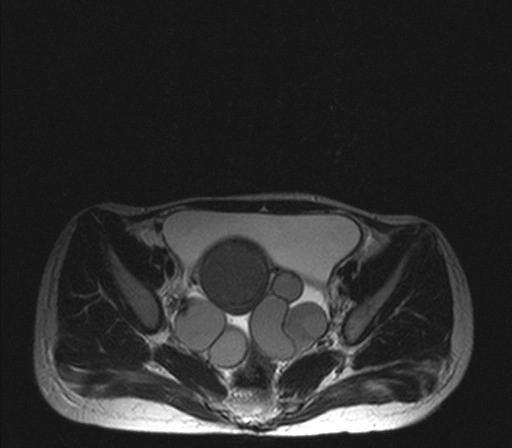

Áp xe vòi trứng - buồng trứng (Tubo-ovarian abscess)